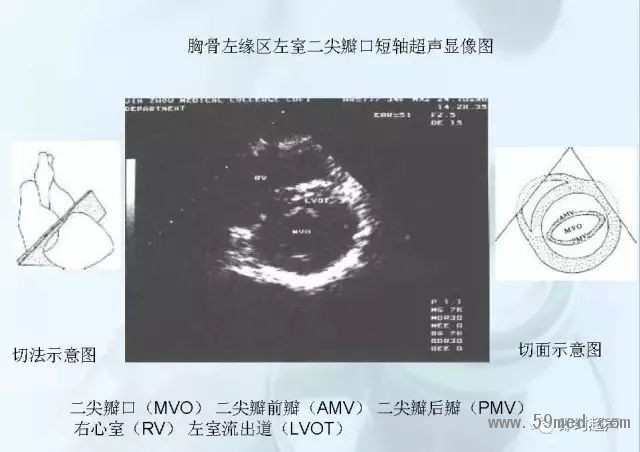

![]() ![]() ![]() ![]() ![]() ![]() ![]() ![]() ![]() ![]() ![]() ![]() ![]() ![]() ![]() ![]() ![]() ![]() ![]() ![]() ![]() ![]() ![]() ![]() ![]() ![]() ![]() ![]() ![]() ![]() ![]() ![]() ![]() ![]() ![]() ![]() ![]() 【注:本文來源于即時超聲,版權(quán)歸原作者所有,如有侵權(quán) 請聯(lián)系 速刪】 =========================== 【閱精彩*悅分享】隨手點擊轉(zhuǎn)至朋友圈,與大家一起分享精彩資訊!當(dāng)然您也可以通過以下方式找到我,與您共同分享藍(lán)韻影像超聲的更多精彩!微信號:landultrasound 電話:+86-0755-66869896 24小時客服熱線:400-888-6452